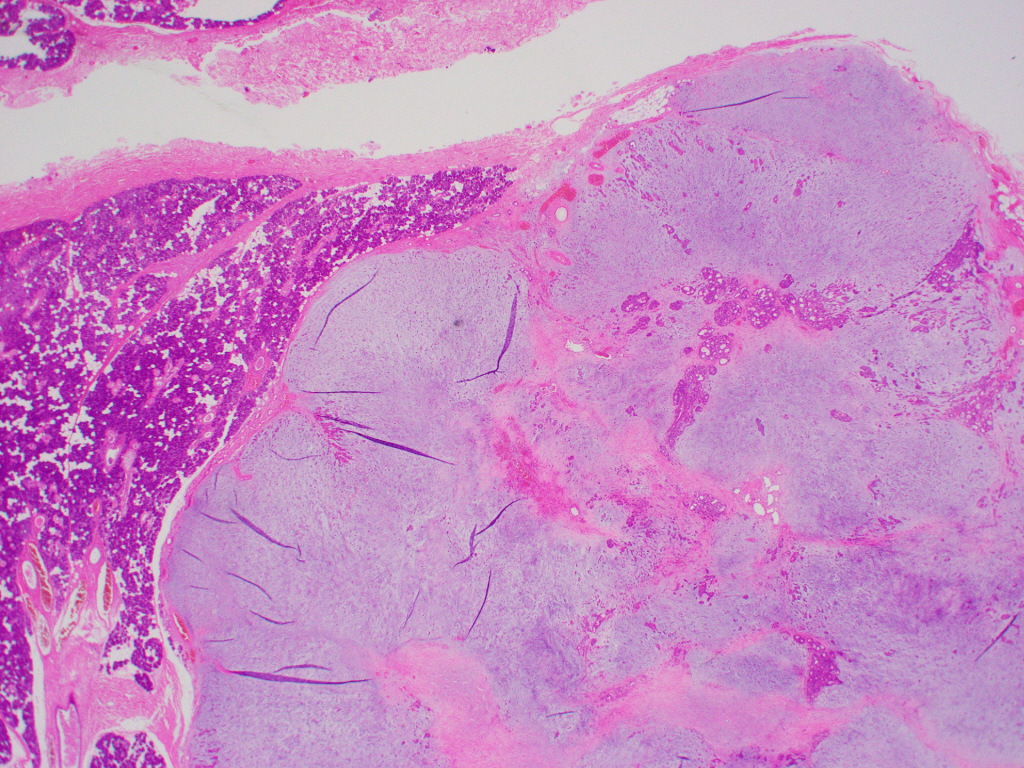

組織標本では、豊富な粘液腫状基質に、星芒状・短紡錘形の筋上皮細胞成分と、管状を示す腺管上皮成分を認める。

腫瘍辺縁には圧排され菲薄化した唾液腺被膜・小葉間結合織を認める。悪性を疑う像は明らかではない。

稀少症例や難解症例ではないが、耳鼻科の標本を見る機会が少ないご施設もあろうと考え、

唾液腺に発生する最も頻度の高い良性腫瘍である多形腺腫の典型像として今回あえてここに供覧した。